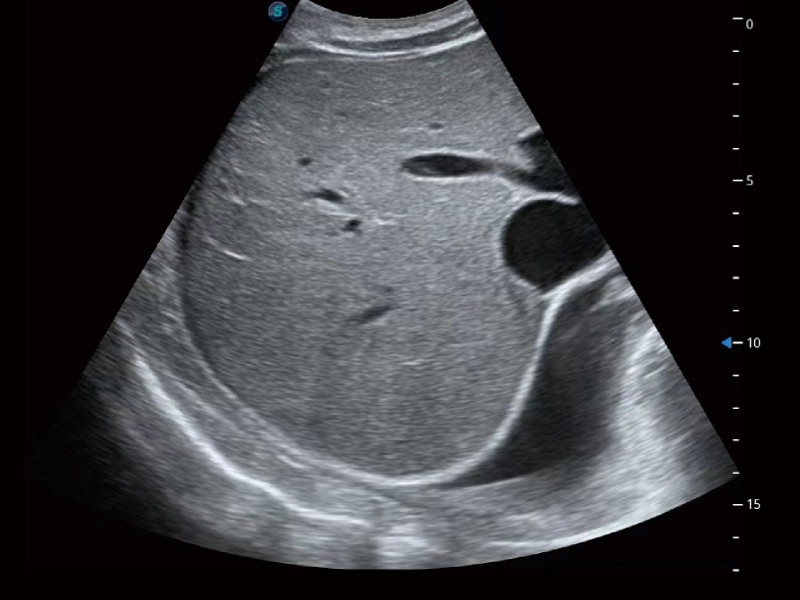

• Abdomen

Líquido ascítico